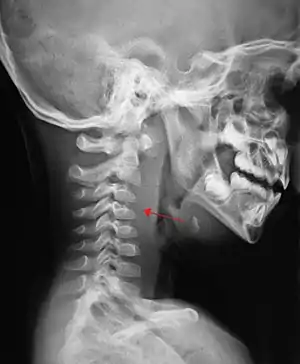

| A lateral cervical spine x-ray demonstrating prevertebral soft tissue swelling (marked by the arrow) as seen in a person with a retropharyngeal abscess. | |

X-ray of the neck often (80% of the time) shows swelling of the retropharyngeal space in affected individuals. If the retropharyngeal space is more than half of the size of the C2 vertebra, it may indicate retropharyngeal abscess.[5]